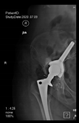

The radiological examination allowed us to verify the close bone-to-implant contact and the unchanged position of the implant during follow-up.

In all the cases operated with the above-described targeting procedure, the stems of the cups remained between the cortical bone surfaces without perforation of the linea terminalis, as shown by postoperative radiographs. There were no complicated surgical situations. In 16 cases, the wound healings were uneventful, and the hips were able to bear weight again after postoperative rehabilitation.

The only patient who suffered an infection healed after the removal of the implant. This complication rate is known and in line with accepted values.

One septic complication occurred. This complication rate is consistent with other revision techniques. In this case, the implant had to be removed, and the patient remained in Girdlestone condition. In such cases, removal of the implants and, of course, surgical debridement and antibiotic treatment are essential. The condition after resection is called Girdlestone’s condition. We had no other complications or unexpected outcomes.

At the time of the manuscript edition, some cases reported in this study were still in the early postoperative period. Even the shortest 10-month follow-up means that patients’ wound healing was uninterrupted, and the implant was securely fixed. By this time, patients are beyond successful rehabilitation. Of course, as with all such patients, monitoring will continue at annual check-ups. Report on the mid and long-term outcomes, gait analysis, and subjective assessments of patients is planned.